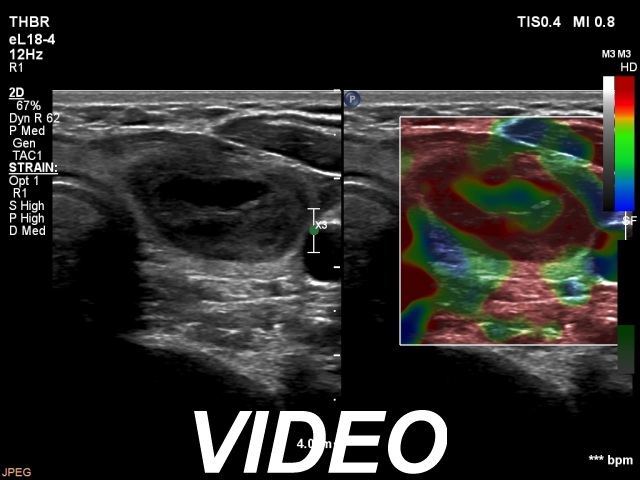

First examination (first and second rows of images)

Clinical presentation: A 39-yr old woman was referred for evaluation of a thyroid cyst which has refilled twice in the past. On the last aspiration, 2 years ago the maximal diameter of the nodule was 24 mm.

Palpation: no abnormality.

Laboratory test: 2.71 mIU/L.

Ultrasonography. The thyroid was echonormal. There was a central-type cystic nodule in the left lobe. The solid portion was echonormal-minimally hypoechoic. The lesion showed back wall cystic figures.Cytology was performed from the lesion in the left lobe and resulted in benign, cystic-colloid goiter.

Suggestion. Ultrasound in two years, in the event of complaints at once. If the cyst would recur ethanol sclerotherapy is advised.